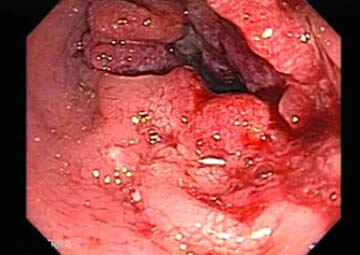

Hình ảnh trĩ nội

Bệnh trĩ nội là 1 tình trạng của bệnh trĩ, là khi các búi trĩ xuất hiện bên trong hậu môn, gây đau rát và có ra máu khi đi đại tiện. Bệnh trĩ nội bao gồm 3 loại: Trĩ nội do tĩnh mạch bị phù: trĩ nội do tĩnh mạch phình gập: trĩ nội do xơ hóa.

- Khi mới bị bệnh trĩ nội các búi trĩ sa ra ngoài hậu môn khi đi đại tiện và tự co lại được, nhưng khi bệnh trở nặng các búi trĩ không thể tự co lại được.

- Vị trí của các búi trĩ nằm ở cuối niêm mạc trực tràng và trên đường lược, bề mặt của các búi trĩ nội cũng là lớp niêm mạc của hậu môn và không có dây thần kinh cảm giác.

- Trĩ nội dẫn đến hiện tượng sa nghẹt búi trĩ, chảy máu và khiến vùng da xung quanh hậu môn bị viêm nhiễm.